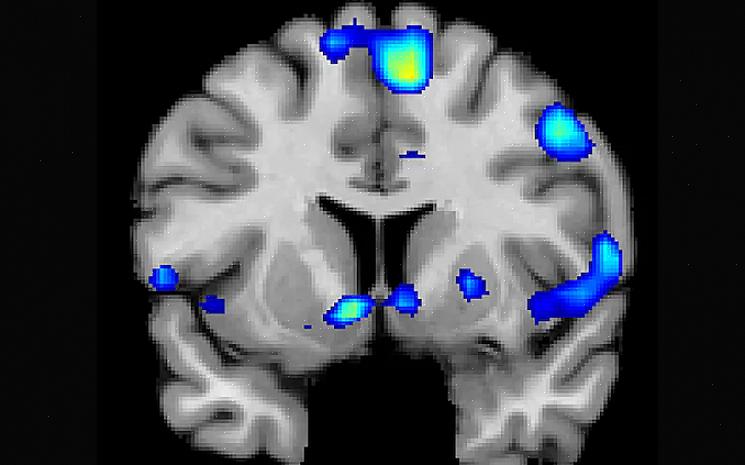

מילר וצוות החוקרים שלה במכון Spirituality mind body השתמשו ב-MRI פונקציונלי כדי להבין מה קרה במוחם של אנשים כשהם דמיינו חוויה רוחנית אינטנסיבית.

הם גייסו אנשים שמוכנים להשתתף בשיטות רוחניות ודתיות שונות. בניסוי הראשון הזה, הם ביקשו מהמשתתפים להיזכר בחוויה רוחנית בזמן שהם עשו סריקת מוח.

לימוד מוחם של המשתתפים בזמן שדמיינו חוויה רוחנית אפשר גם למדענים לזהות את אזורי המוח שיש להם חלק בעיבוד חוויות רוחניות.

מילר ועמיתיה גם השוו את פעילות המוח בשני רגעים שונים: כשהמשתתפים תיארו חוויה רוחנית ובזמן שהם דמיינו חוויות מלחיצות או ניטרליות שלא עוררו רגשות חזקים.

במהלך הניסויים הללו, הם צפו בדפוס שהתרחש רק במהלך חוויות רוחניות. הם אמרו שהמשתתפים הפחיתו את פעילות האונה הקודקודית התחתונה כאשר תיארו אירוע רוחני. כפי שהזכרנו לעיל, חלק זה במוח קשור למודעות עצמית ומודעות של אחרים. מצד שני, פעילות זו גדלה כאשר המשתתף חשב על דברים מלחיצים או ניטרליים.

כתוצאה מכך, צוות המחקר מציע שאזור מסוים זה עשוי למלא תפקיד משמעותי ברגעים אלה. זה רלוונטי לעיבוד תפיסה וייצוג עצמי של האחר במהלך חוויות רוחניות. נראה שזה תומך ברעיון שחוויות רוחניות יכולות לעזור לרכך את השפעת הלחץ על הבריאות הנפשית.